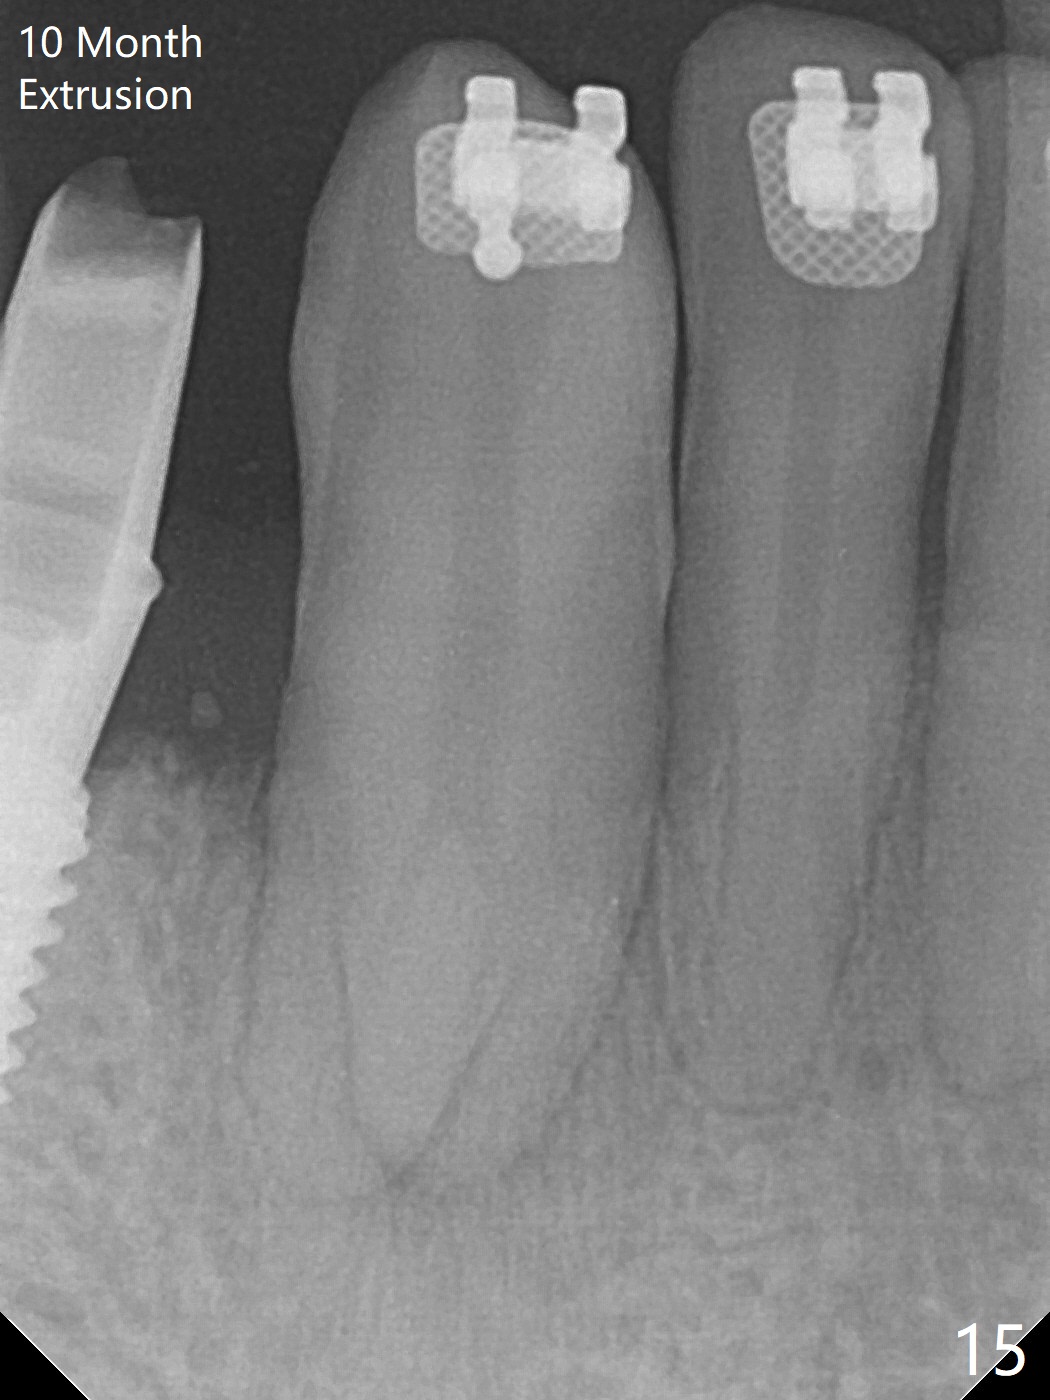

When the surgical guide for #28 is removed, the 4x13 mm implant is found to be superficial and buccal. Part of the buccal mucosa is nonkeratinized. After 1 mm deeper placement of the implant, CT confirms the buccal placement (Fig.1, as compared to design). In fact the guide was doubly checked for fitness prior to osteotomy, but grossly it seemed to be seated properly. The suspicion is related to the trimming at the site of #27 (Fig.2,3 (*), as compared to a mounted model in Fig.4,5 (arrowhead) and the model sent to lab for guide fabrication). The lab agrees to redesign the case. There is a narrow buccal band 1 week postop (Fig.6). The patient is a smoker. The implant was placed buccal (Fig.7, 1 month postop). A new 4x13 mm implant is placed on the top of the 1st line following 3x14.5 mm drill (Fig.8 (35 Ncm)). In fact the implant position is not changed much. Four months post banding (20 ss) and 2 months post 2nd implant placement, the tooth #27 is exposed for bracket; extrusion is initiated (Fig.9). In 3 weeks of retraction, the bracket is supragingival (Fig.10). The canine contacts the distal healing abutment with 2 months of retraction (Fig.11). It seems necessary to initiate lower bracket placement. There is no bone loss 4 months postop (Fig.12). A 4.5x7(4) mm abutment is placed (Fig.13) for a temporary crown as an anchor (Fig.14) to further extrude #27 with continuous inter-arch retraction (to reduce tension upon #26 with severe bone loss (Fig.12)). LR3 extrusion is incomplete, although there is an increase in bone distal to LR2 ~ 10 months of extrusion (Fig.15).